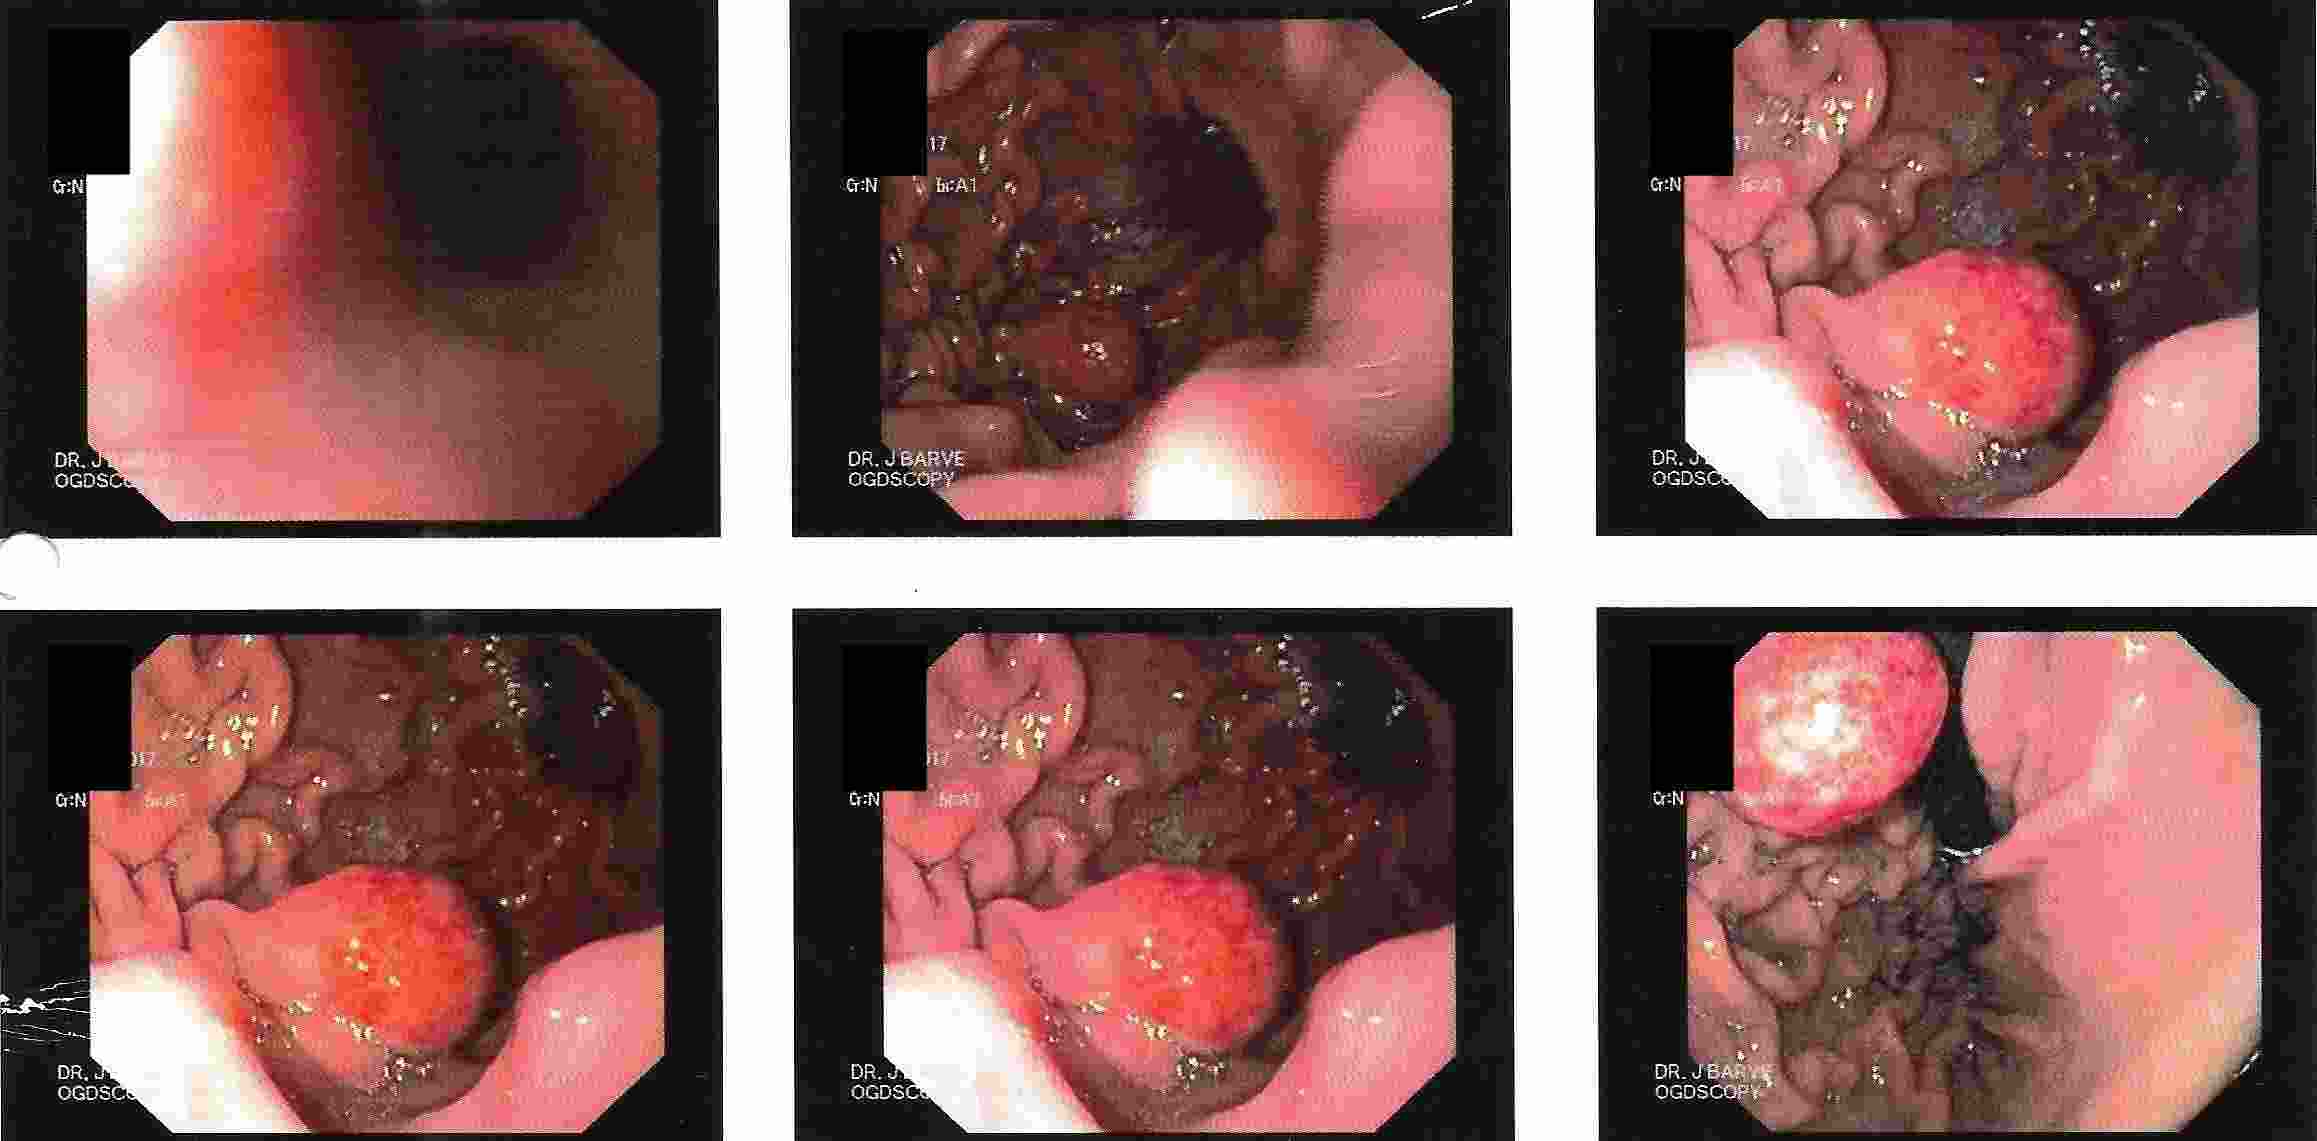

Tumours of the Stomach

Polyps of the Stomach